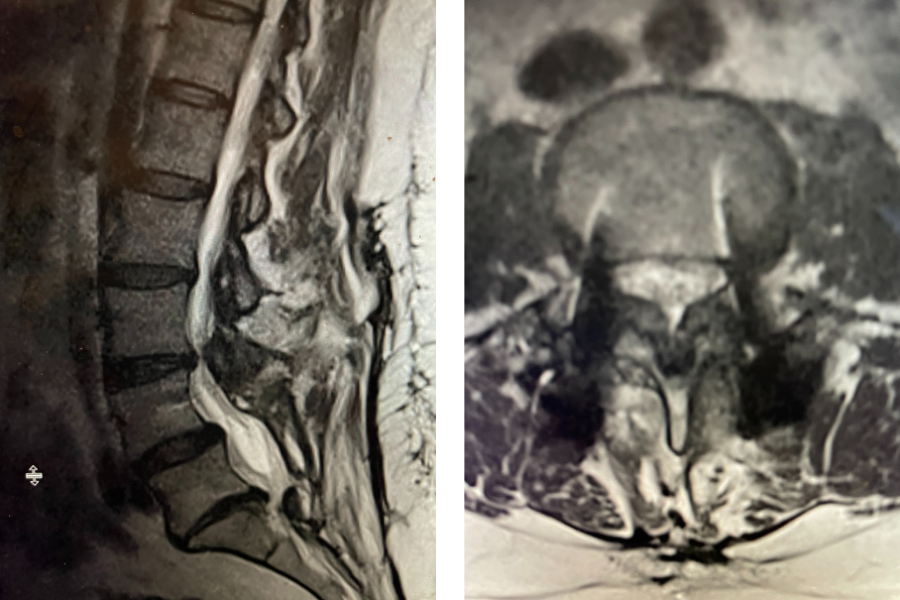

Figure 2. Illustration demonstrating an example of a lumbar In Situ fusion with bone graft material placed on top of transverse processes

At the time of surgery, it was noted that she had not only a very solid L4-S1 fusion but also her hardware was 100% encased in the bone. It was so much so that we decided not to remove this bone as we felt it would cause excess blood loss and perhaps add risk to neurological injury because of the force sometimes necessary to essentially “chisel” out this bone. We decided as a compromise, given her relatively young age and risk of redeveloping stenosis in the future, was to perform an “in situ” fusion from L2 to the top of the prior L4 fusion mass. It is to be remembered that the signal to form lumbar stenosis does not disappear once a laminectomy is performed, and a fusion prevents that signal. An “in situ” fusion is one where bone graft material is placed on the sides of the spine along bony extensions called transverse processes (Fig 2). The purpose of these processes besides serving as an excellent scaffold for bone graft material they also attach the back muscles or “paraspinal muscles” that allows a side or lateral bending motion or twisting. This way the patient will have reasonable stability after the bone consolidates and fuses. It has been found that a patient may not have to, with an in-situ fusion, have it be perfectly solid for it to serve the purpose of providing stability. The patient had an uneventful postoperative course.